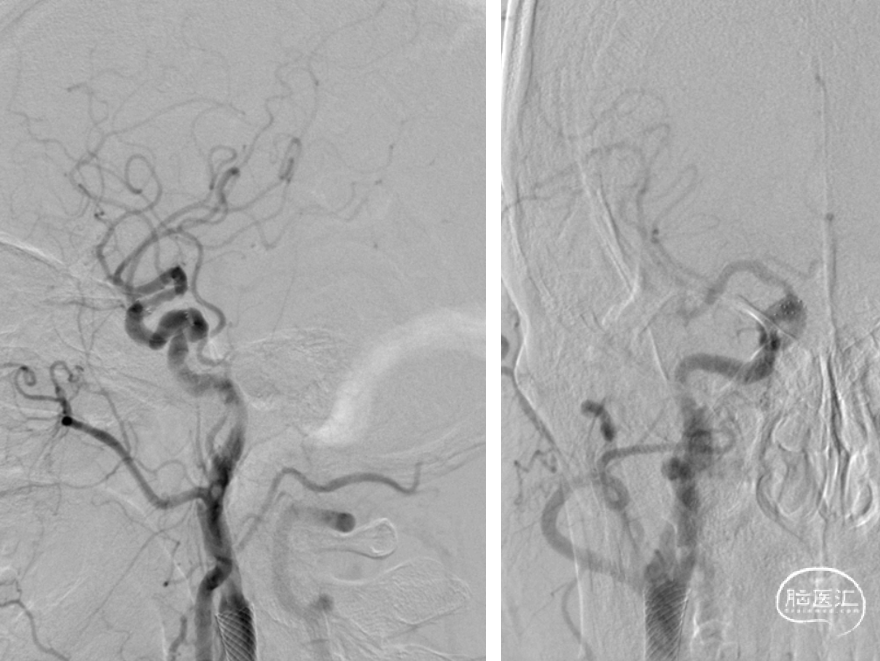

术后即刻造影

术后半年复查DSA